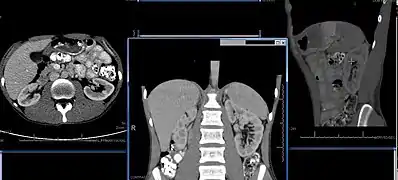

Imaging

Renal ultrasonography is essential in the diagnosis and management of kidney-related diseases.[35] Other modalities, such as CT and MRI, should always be considered as supplementary imaging modalities in the assessment of renal disease.[35]